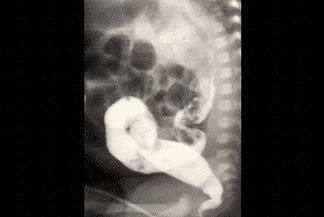

Texto alternativo para a imagem Figura 2. Crédito: Dra. Elazir Mota - Rio de Janeiro/RJ

Descrição das imagens: Clister opaco. Administra-se contraste baritado diluído por sonda retal, seguido da realização de radiografias em AP e perfil. Observa-se, já na fase de enchimento, a desproporção entre calibre do reto e sigmoide, sendo o reto bem menor (figuras 2 e 3). A radiografia simples do abdome em perfil auxilia na suspeição diagnóstica pela não visualização de gás na ampola retal (figura 1).

• Clister opaco: Exame de escolha no quadro de constipação intestinal crônica na população pediátrica. É realizado com paciente na sala de radiografia, com cateterização retal e instilação de contraste baritado diluído por via retal. O contraste deve progredir pelo menos até a flexura esplênica. Seu principal objetivo é afastar a possibilidade de aganglionose colônica, causa cirúrgica de constipação intestinal. Nestes pacientes com aganglinose, observa-se inversão do índice retossigmoideano (reto menor que o sigmoide) e visualização do cone de transição. Podem ser necessárias radiografias tardias - 24 horas após a realização do clister. Importante ressaltar que, no exame normal, o reto deve ter calibre maior ou igual ao do sigmoide.